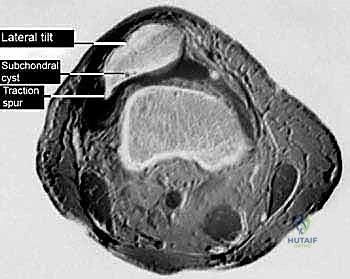

* CT Scan: The gold standard for evaluating patellar tilt. An axial image is used to draw a line parallel to the posterior femoral condyles and compare it to a line along the lateral patellar facet. If these lines converge laterally, it indicates excessive lateral tilt.

FIG 1 • B. Axial CT image of a right knee demonstrating how to measure patellar tilt.

* MRI Scan: Beneficial for assessing articular cartilage integrity, meniscal tears, and ligamentous pathology, which can often coexist. It can also demonstrate the extent of lateral retinacular thickening.

FIG 1 • C. Axial MRI scan of the right knee of a patient with excessive lateral pressure syndrome.